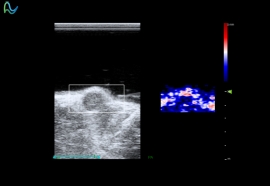

高频超声成像